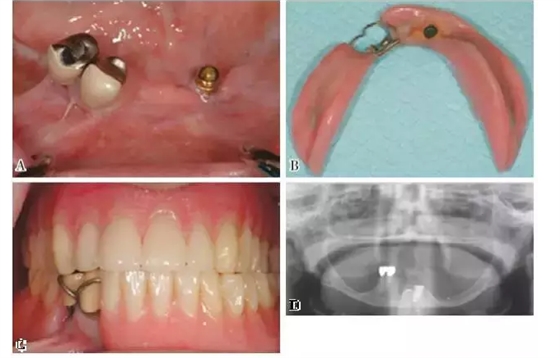

圖3:下頜KennedyⅠ類缺損。 剩余牙槽嵴顯著吸收伴有22號牙的缺失。種植體的使用提供了足夠的固位力,改善了義齒的舒適性和咬合功能